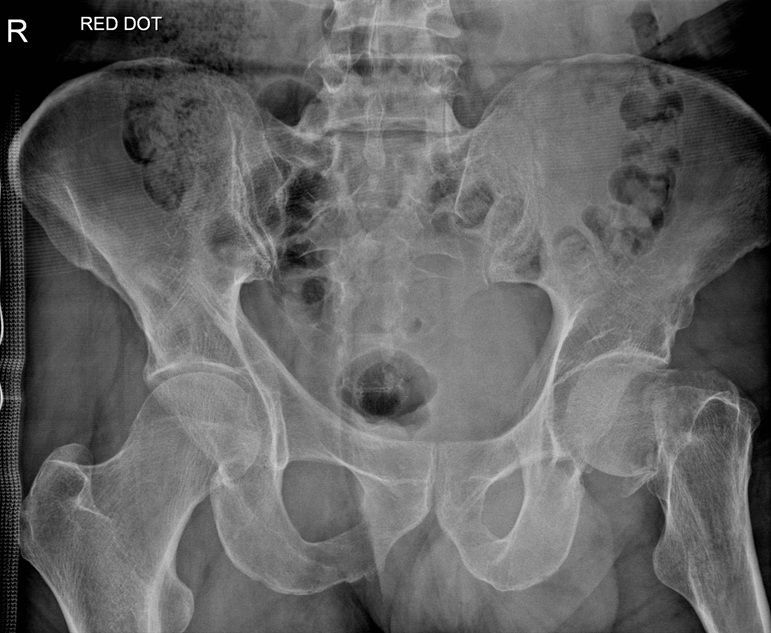

Question 3

Question

Which operation would you perform?

Answer

• THR

• Hemiarthroplasty